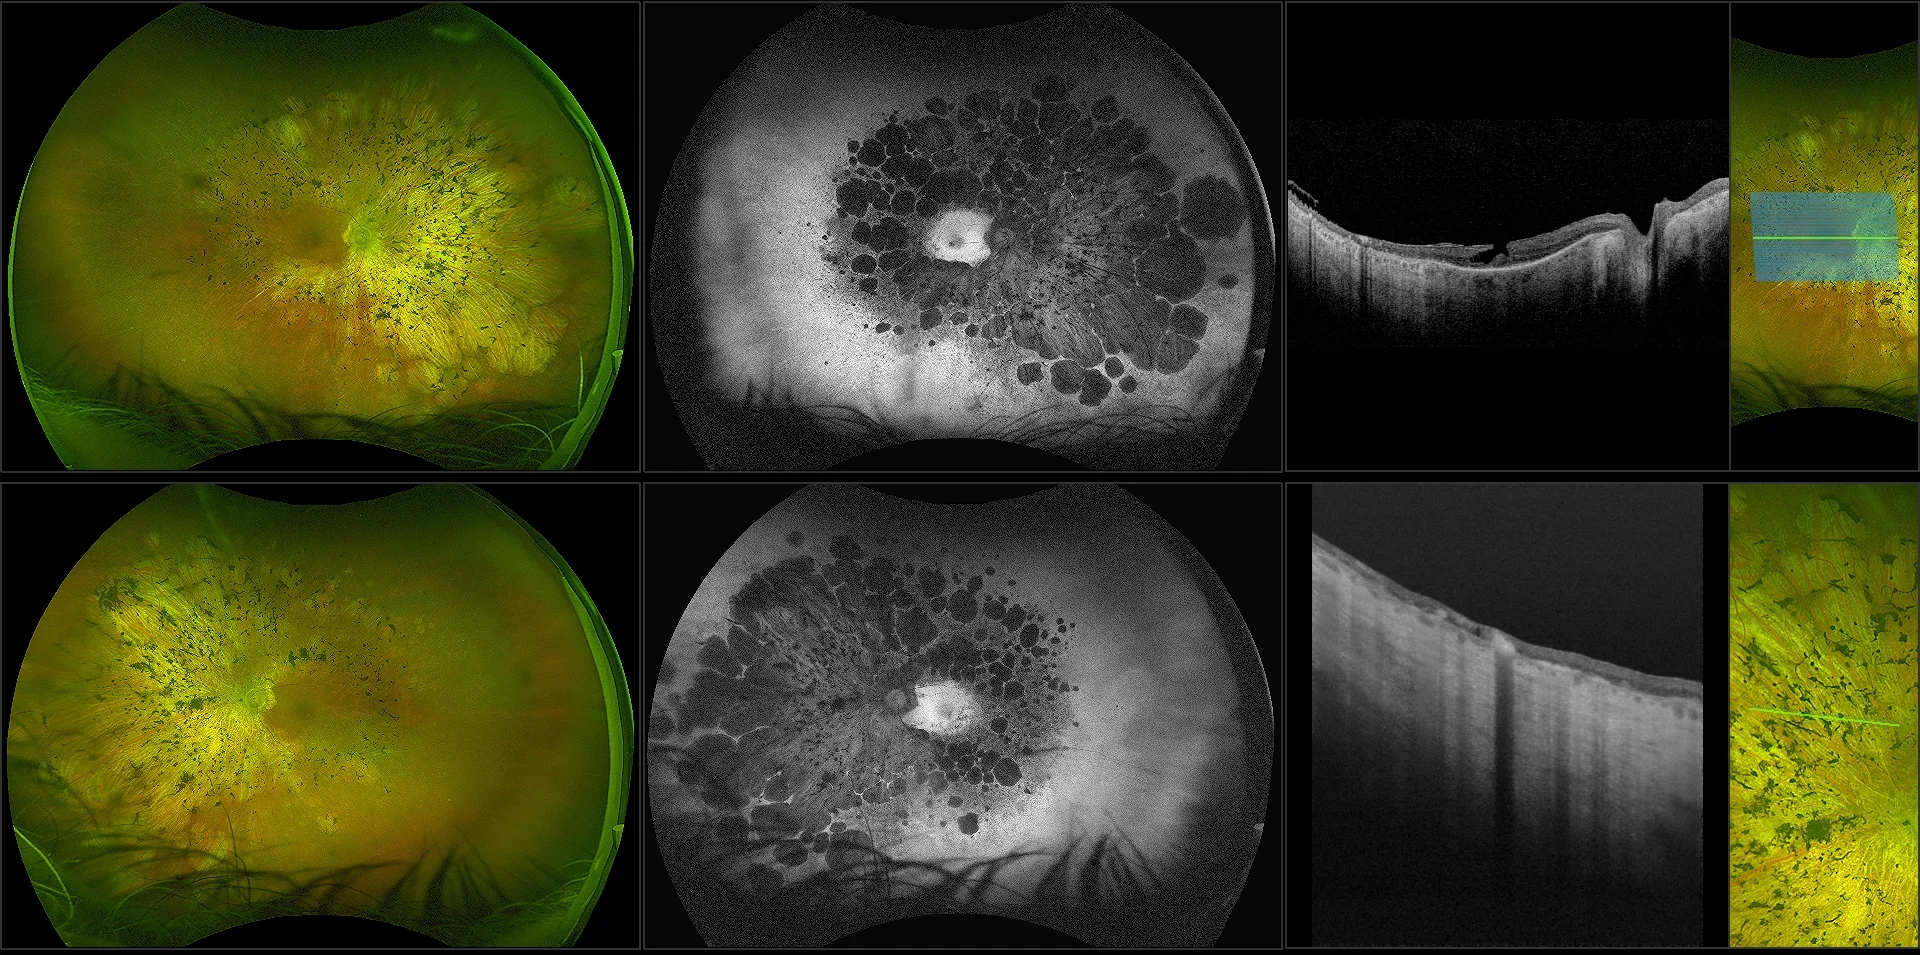

MonacoPro - Vitreous Floaters, RG, OCT

Vitreous floaters are microscopic collagen fibers within the vitreous that tend to clump and cast shadows on the retina, appearing as floaters to the patient.